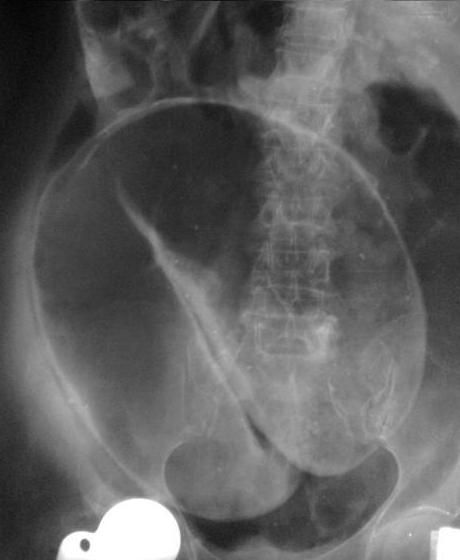

Image radiologique ASP de occlusion du

colon est : Aspect de distension de air du colon avec

collapse du colon en aval . Image de niveaux hydroaerique

avec aspect la hauteur plus que la largeur et situe

peripherique de l'abdomen . L'intestin grele se dilate

encore selon la duration de l'occlusion et l'incompetence de

la valvule Bauhin . Dans les cas l'obtruction par colite

ischemique on peut voyait image pneumatosis de la paroi du

colon ou image d'air du syteme portale . L'occlusion

par volvulus se donne de image tres particuliairement :

Image hydro-aerique du colon d'une

occlusion du colon . Aspect du colon en distendue

avec image des plies des haustrals de cette bord en

intercale avec des haustrals du bord oppose |